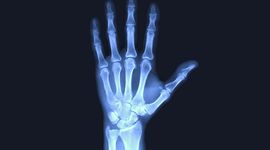

Deși discuțiile despre schimbările climatice ne duc de obicei cu gândul la ghețari care se topesc sau la nivelul mărilor în creștere, degradarea rapidă a planetei pare să ne afecteze și organismul în moduri surprinzătoare: dioxidul de carbon (CO2) atmosferic devine atât de ridicat încât slăbește oasele oamenilor.

Un studiu recent sugerează că creșterea concentrației de dioxid de carbon din atmosferă slăbește oasele oamenilor într-un ritm îngrijorător.

Rezultatele au arătat că, începând cu finalul secolului al XX-lea, cantitatea de bicarbonat din sângele uman a crescut cu aproximativ 7%. Această evoluție a urmat îndeaproape creșterea concentrației de CO2 din atmosferă.

În același timp, cercetătorii au analizat și nivelurile de calciu și fosfor din organismul adulților americani. Ambele minerale au înregistrat o scădere pe parcursul perioadei studiate.

Autorii studiului avertizează că această coincidență nu este întâmplătoare. Atunci când sângele conține mai mult carbon decât este obișnuit pentru organism, oasele eliberează calciu și fosfor pentru a ajuta la absorbția unei cantități mai mari de CO2.

În condiții normale, înainte ca activitatea umană să crească masiv poluarea atmosferică, oasele ar reabsorbi aceste minerale în decurs de câteva săptămâni. Dacă însă nivelurile ridicate de carbon din sânge devin permanente, acest echilibru delicat poate fi perturbat. În timp, organismul ar putea pierde treptat calciu, ceea ce ar duce la slăbirea oaselor aproape tuturor oamenilor care respiră aerul planetei, dar și la alte probleme de sănătate, scrie Futurism.

Cercetătorii consideră că fenomenul devine deja suficient de evident încât ar putea provoca efecte serioase asupra sănătății în aproximativ 50 de ani.

Pe baza tendințelor observate, cercetătorii estimează că nivelul de carbon din sânge ar putea ajunge în următorii 50 de ani la „limita superioară acceptată a intervalului considerat sănătos”, în timp ce nivelurile de calciu și fosfor ar putea coborî la pragurile minime considerate normale.